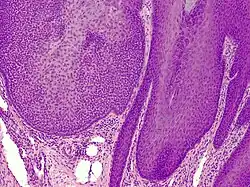

Trichilemmoma

Trichilemmoma (also known as "tricholemmoma"[1]) is a benign cutaneous neoplasm that shows differentiation toward cells of the outer root sheath.[2]: 673 [3] The lesion is often seen in the face and neck region. Multifocal occurrence is associated with Cowden syndrome, in which hamartomatous intestinal polyposis is seen in conjunction with multiple tricholemmoma lesions.